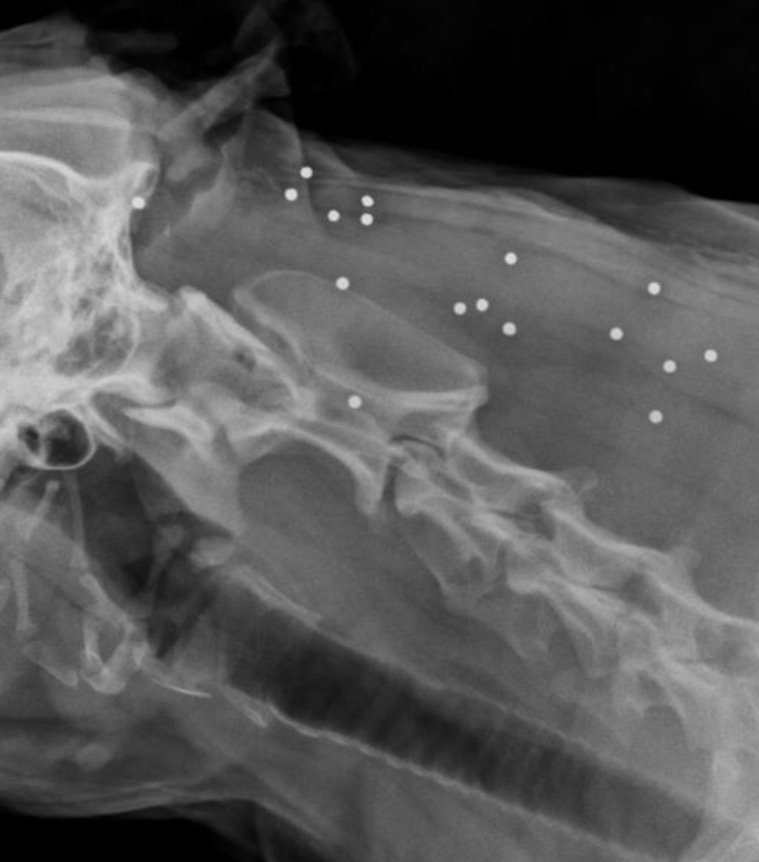

(PDF) Lead Poisoning in Dog Case Report Didier Quevedo Cagnini Lead Poisoning In Dogs But, despite its discontinued use in paint and gasoline, lead can still be found in food,. And while it’s not a common issue in dogs and cats, cases of lead toxicity do happen, so the aspca animal poison control center offers this primer. Lead poisoning occurs when lead accumulates in the body, usually after being inhaled or ingested. Lead intoxication. Lead Poisoning In Dogs.